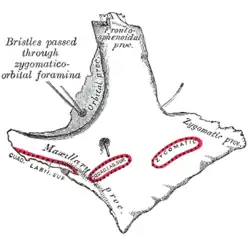

Osso zigomático esquerdo. Superfície de Malar.

Osso zigomático esquerdo. Superfície de Malar. Osso zigomático esquerdo. Superfície temporal.

Visão lateral do crânio. Fossa infratemporal esquerda.

Fossa infratemporal esquerda. O crânio da frente.